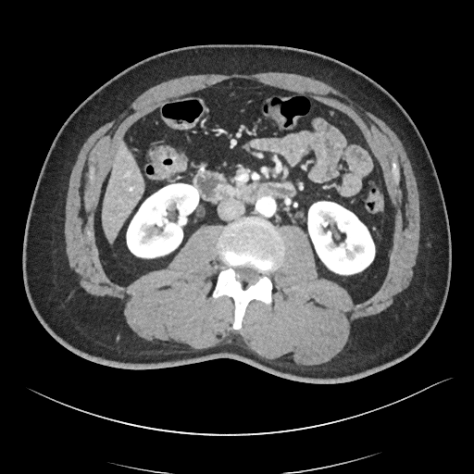

4.8 Real Clinical Evaluation

We also evaluated the proposed CAP-IQA model on an in-house dataset. Fig. 8 displays sample images from the dataset. We retrospectively collected real clinical CT images from the University of Kentucky Medical Center with approval from the Institutional Review Board. A total of 91,514 image slices from 336 pediatric patients aged 2-12 years were used for testing the generalizability of CAP-IQA. Since these images have already been used for clinical diagnosis, they are expected to be of high quality (>3, as per the IQA scoring criteria in Table 1). Slice-wise IQA scores predicted by the model were averaged to obtain the overall score for each of the CT scans. The average IQA score across the 336 pediatric scans is 3.8582, with a correlation of variation of 2.1447. As seen in Fig. 9, the predicted scores are tightly grouped around the mean, with scores above the diagnostic-quality threshold of 3. The relatively high predicted scores align with expert radiologists’ assessments, indicating that the scans retain good diagnostic quality. Overall, the results demonstrate that CAP-IQA performs reliably in real-world clinical settings, and the model consistently and accurately assesses quality across diverse patient data.

![]() |

| 3.95 | 3.71 | 3.94 |

| 3.46 | 3.79 | 3.55 |